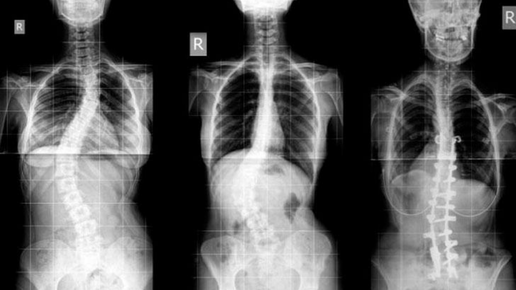

Диафрагма и боль в спине